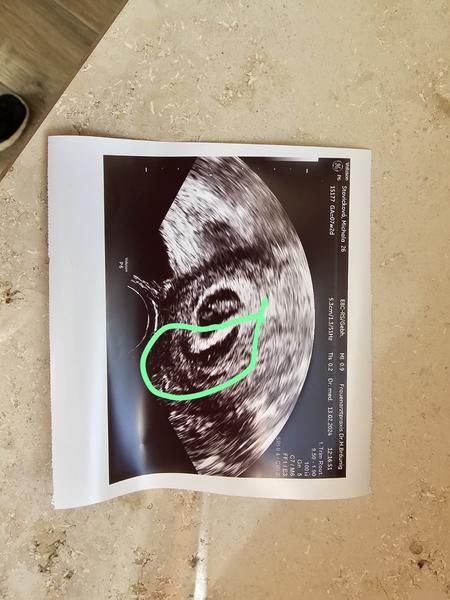

Ahoj, tak konečně srdecni akce ale udělal se hematom kolem delohy cca 2cm. Dneska jsem slabé krvácela.